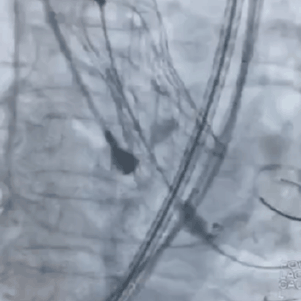

患者全麻后,经右颈内静脉植入临时起搏器,行双侧股动脉穿刺。右侧股动脉入路,跨瓣完成后160 bpm起搏下预24mm球囊扩张主动脉瓣,球囊完全扩张后,发现左冠显影延迟,右冠显影,在心内科刘巍,王志坚教授协助下行左侧冠脉保护,精准释放VitaFlow30# 瓣膜;瓣膜释放完成后,造影显示左右冠显影正常,遂撤出保护球囊。术后病人生命体征平稳,无明显瓣周漏、跨瓣压差明显改善。

术中精彩视频:

瓣膜通过输送系统送至释放点

术后造影